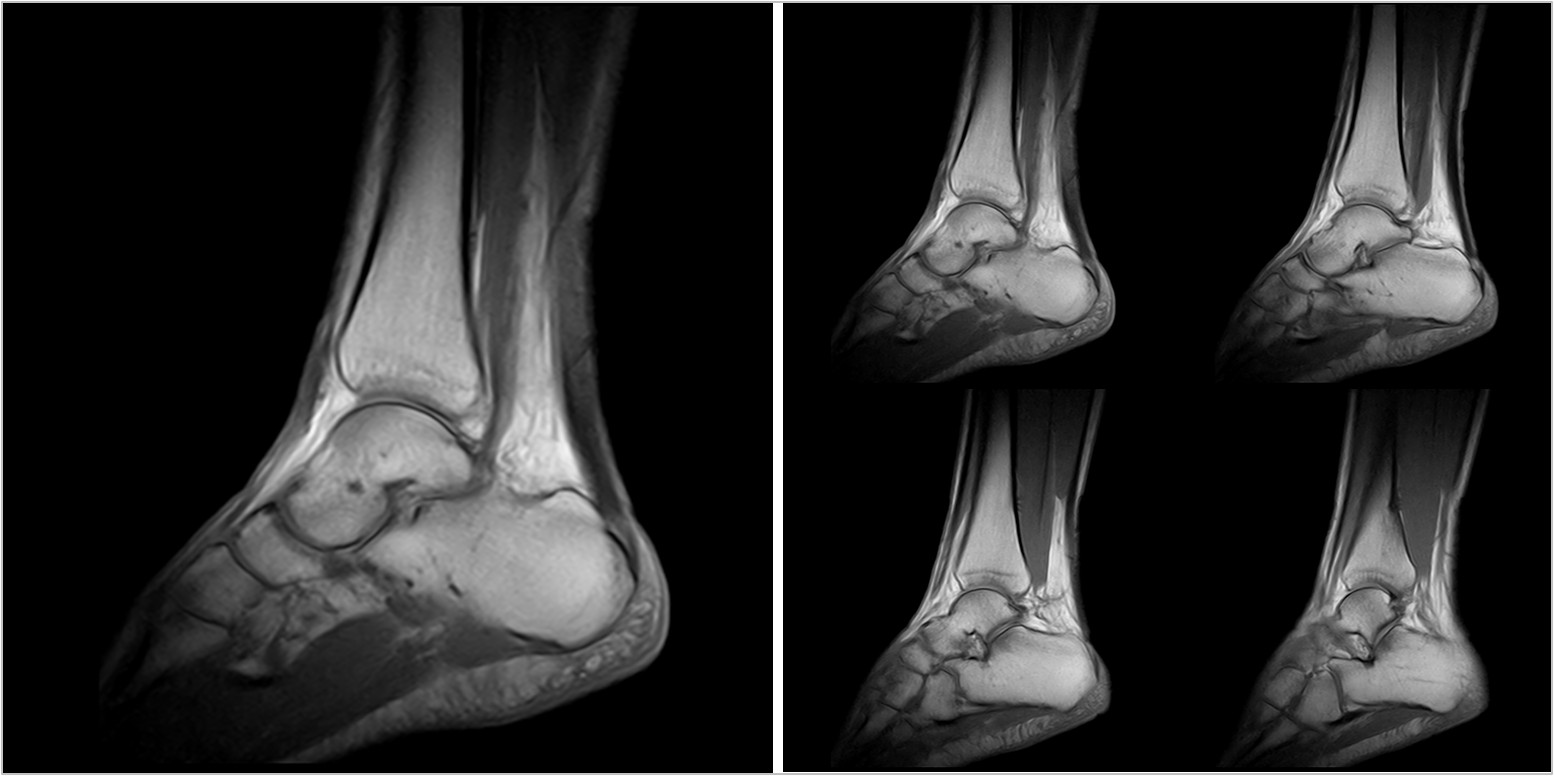

Hình ảnh lâm sàng